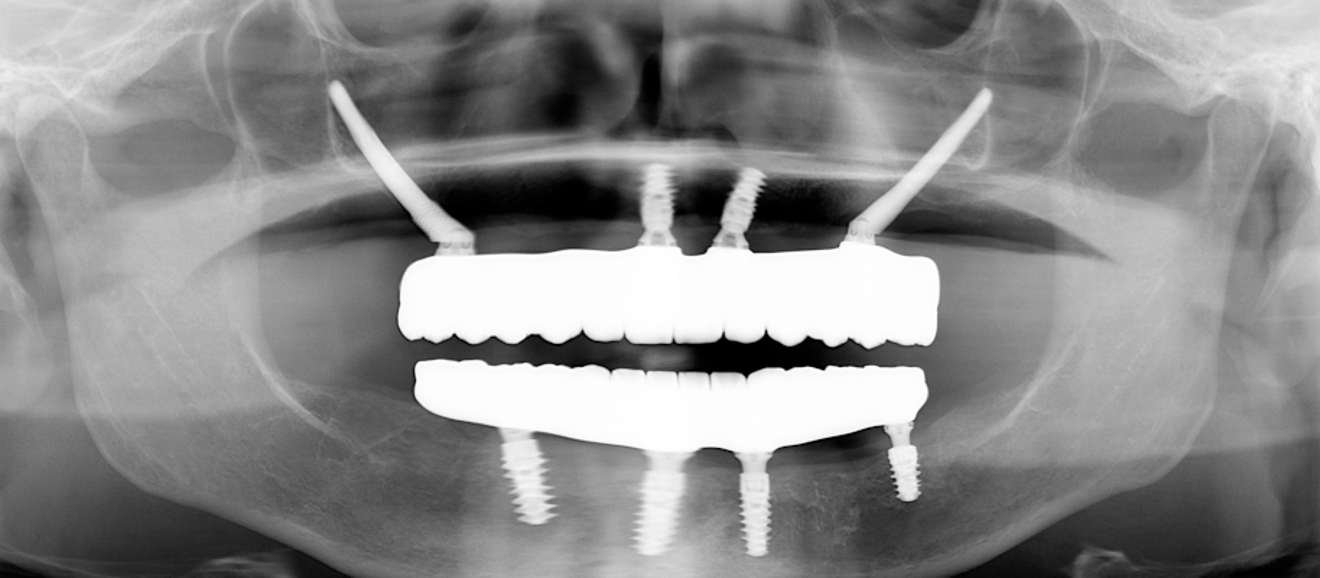

The treatment was carried out under local anaesthesia with 2% lidocaine and 1:100,000 adrenaline. A crestal incision was made and a full-thickness mucoperiosteal flap raised. The implant beds were prepared with the Straumann Surgical Cassette, and two Straumann BLX implants (4.5 × 10.0 mm, SLActive, Roxolid) and two Straumann zygomatic implants (4.3 × 40.0 mm) were placed in the maxilla (Fig. 8). Following the same protocol, four Straumann BLX implants (4.5 × 10.0 mm, SLActive, Roxolid) were inserted in the mandible. Straumann screw-retained abutments were positioned on to the implants (Fig. 9).

Fig. 8